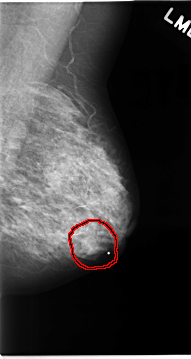

C_0064_1.LEFT_MLO

FILE: C_0064_1.LEFT_MLO.OVERLAY

TOTAL_ABNORMALITIES 1

ABNORMALITY 1

LESION_TYPE MASS SHAPE OVAL MARGINS CIRCUMSCRIBED

ASSESSMENT 3

SUBTLETY 5

PATHOLOGY BENIGN

TOTAL_OUTLINES 1

BOUNDARY